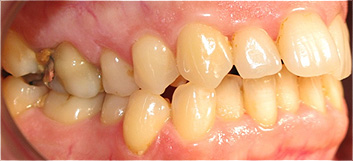

Apinhamento dentário severo e ausência do dente canino (dente 23).

![]() |

Após o tratamento ortodôntico e colocação de prótese fixa de cerâmica, para colocação do dente canino.